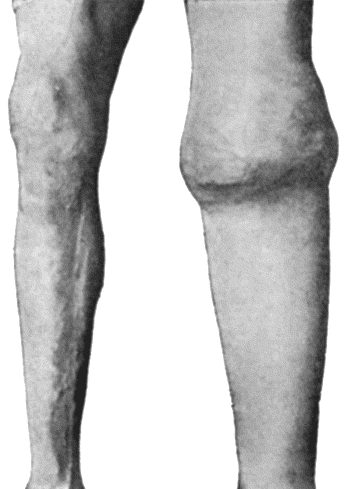

| 14. | Leg Ulcers associated with Varicose Veins | 71 |

| 19. | Tibia and Fibula, showing changes due to Chronic Ulcer of Leg | 80 |